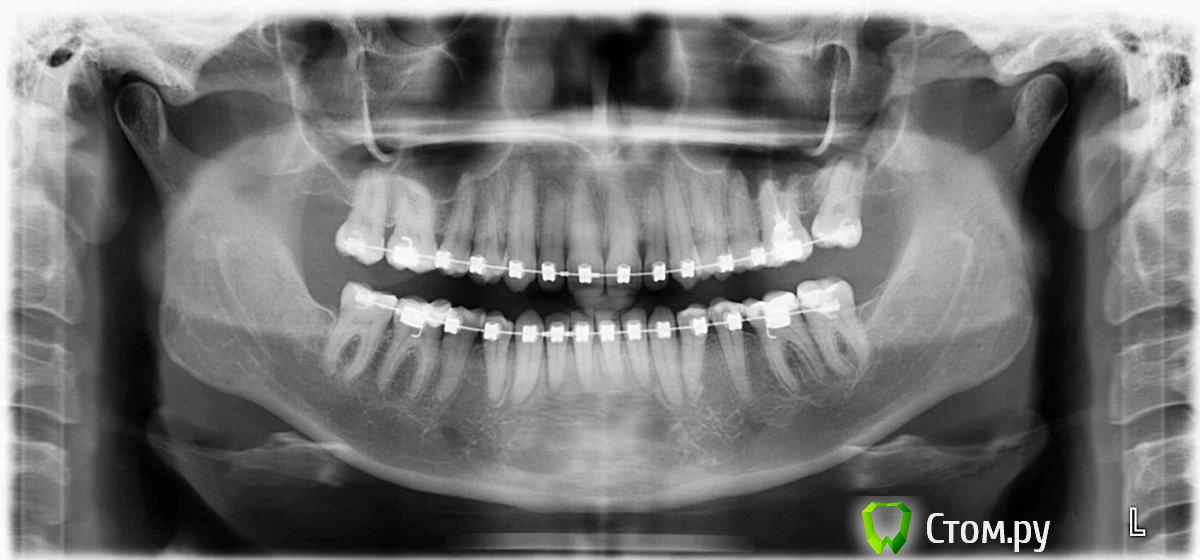

eva12 Опубликовано 8 апреля, 2014 Поделиться Опубликовано 8 апреля, 2014 (изменено) Доброго времени суток! Беспокоит 34 зуб если нажать на брекет, на 35 клиновидный дефект ( со слов доктора), 37( как мне кажется) есть повторный кариес, видна граница пломбы и я могу зацепиться за нее ногтем. Консультировалась в двух клиниках, постучали-посмотрели, сделали снимок и отпустили. Можно ли что-то увидеть на снимке с брекетами, мне кажется брекет закрывает пломбу и рассмотреть вторичный кариес невозможно, или я ошибаюсь? 34 зуб беспокоит очень, реагирует на горячее, что с ним делать? Выкладываю снимок до и во время лечения брекет-системой Изменено 8 апреля, 2014 пользователем eva12 Ссылка на комментарий

Гарриевич Опубликовано 9 апреля, 2014 Поделиться Опубликовано 9 апреля, 2014 Не ешьте горячего... Шутка)Вам нужен очной осмотр, по тем снимкам которые выложены ничего патологического не видно. Можете сделать прицельный снимок беспокоящих зубов и выложить, будет яснее картина Ссылка на комментарий

DmitrySH Опубликовано 9 апреля, 2014 Поделиться Опубликовано 9 апреля, 2014 Поддерживаю, на снимке ничего патологического не видно. Ссылка на комментарий